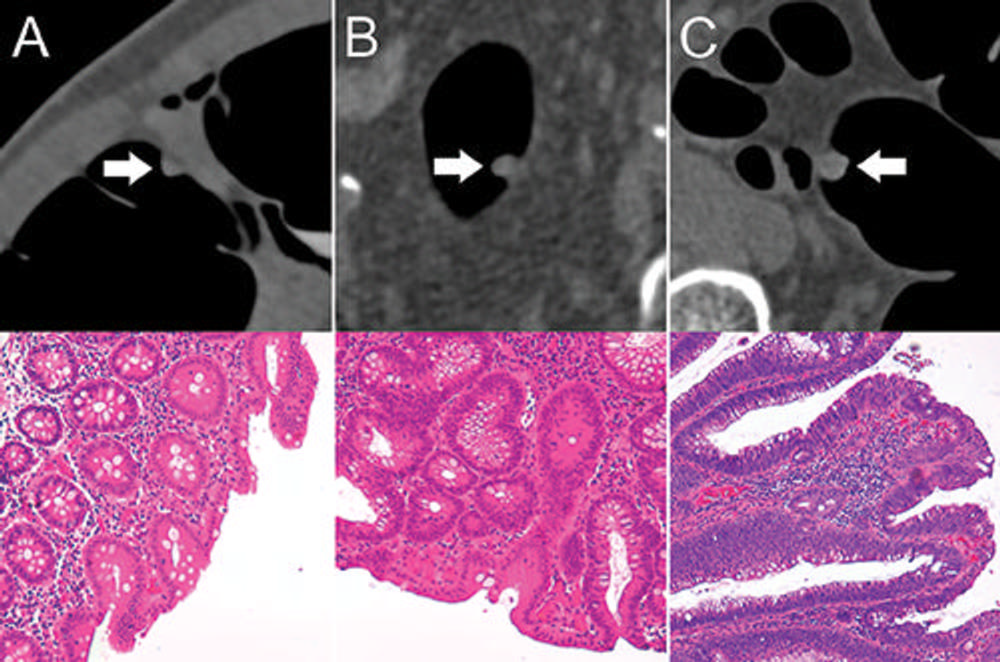

Figure 3. Top: Axial CT colonography images show representative colorectal polyps (arrow) in the training set. Bottom: Corresponding histopathologic work-up. (Hematoxylin-eosin staining; original magnification 320.) A, An 8-mm hyperplastic polyp in the ascending colon of a 54-year-old woman with hyperplastic epithelia. B, An 8-mm tubular adenoma in the sigmoid colon of a 68-year-old man with tubular growth pattern and elongated nuclei. C, An 11-mm tubulovillous adenoma in the rectum of a 73-year-old man with tubulovillous growth pattern and elongated nuclei.